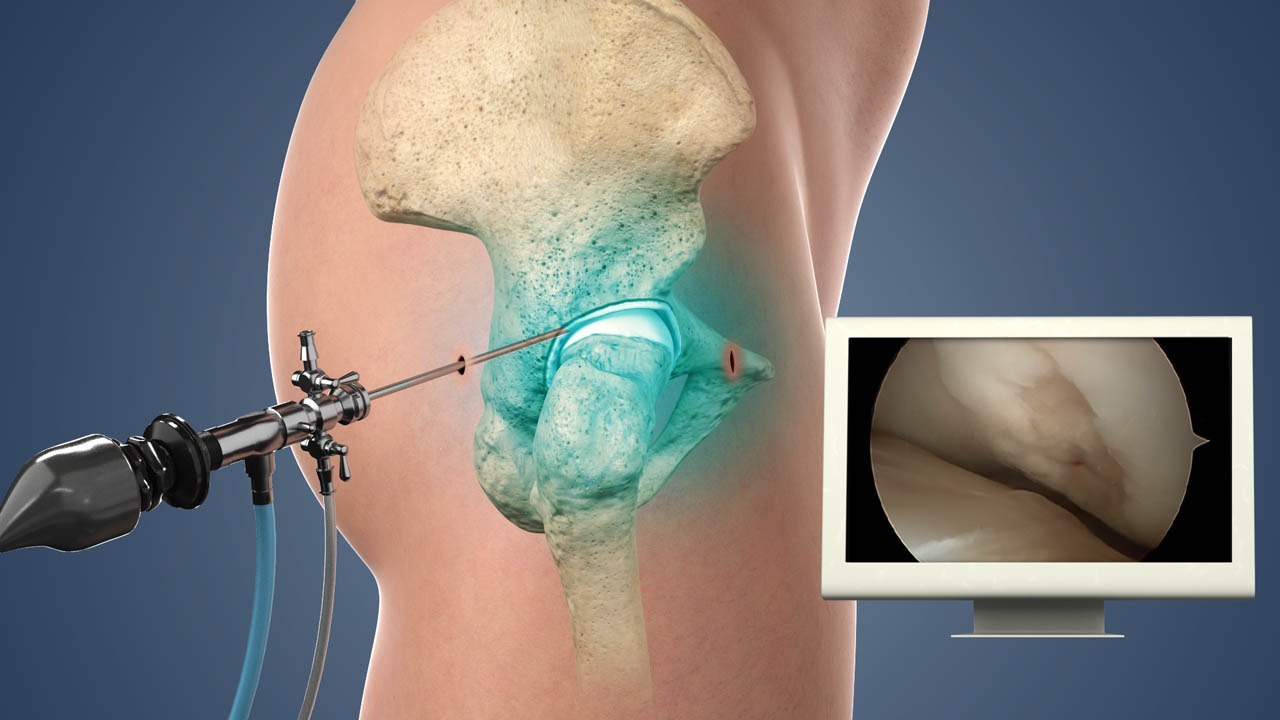

What Is Arthroscopic Surgery and How Does It Work?

Did you know that arthroscopic surgery allows surgeons to examine, diagnose, and treat joint problems without making large incisions? If you’re planning to undergo arthroscopy,